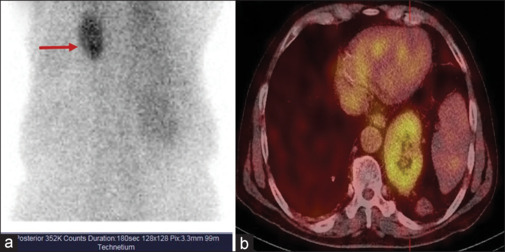

胸内肾非常罕见,在所有肾异位中发病率最低。我们报告的情况下,70岁的男性谁被转介二乙烯三胺五乙酸(DTPA)扫描作为术前工作的一部分,为右肾肿块。腹部超声检查错误报告左肾位置正常。99mTc-DTPA肾脏扫描联合单光子发射计算机断层扫描-计算机断层扫描显示左肾异位(胸腔内)肾小球滤过率受损。18-氟脱氧葡萄糖正电子发射断层扫描-计算机断层扫描图像显示软组织肿块完全取代右肾并转移到双侧肺。本病例再次强调了核医学成像在诊断和评价胸内肾功能中的重要性。

Intrathoracic kidney is very rare and has the lowest prevalence among all renal ectopias. We report the case of a 70-year-old male who was referred for diethylenetriaminepentaacetic acid (DTPA) scan as a part of presurgical work-up for a right renal mass. PriorUltrasonography abdomen incorrectly reported left kidney as normal in location. 99mTc-DTPA renal scan combined with single-photon emission computed tomography - computed tomography revealed impaired global glomerular filtration rate with left kidney in ectopic (intrathoracic) location. 18-fluorodeoxyglucose positron emission tomography-computed tomography images revealed a soft tissue mass completely replacing the right kidney with metastases to bilateral lungs. This case reemphasizes the importance of nuclear medicine imaging in diagnosis and evaluation of the renal function of the intrathoracic kidney.